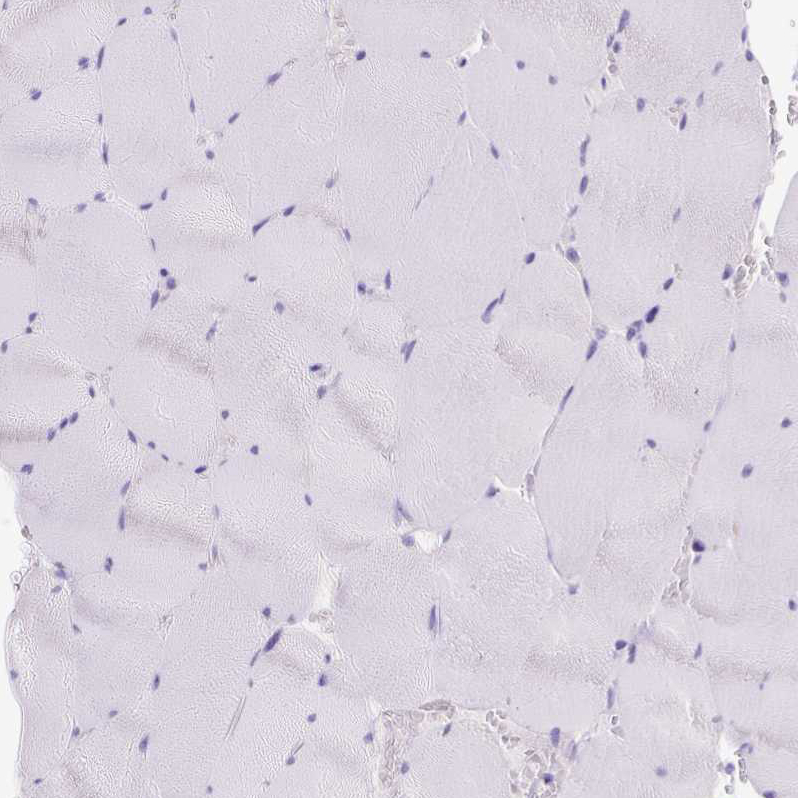

Immunohistochemistry analysis in human pancreas and liver tissues using HPA052701 antibody. Corresponding CEL RNA-seq data are presented for the same tissues.